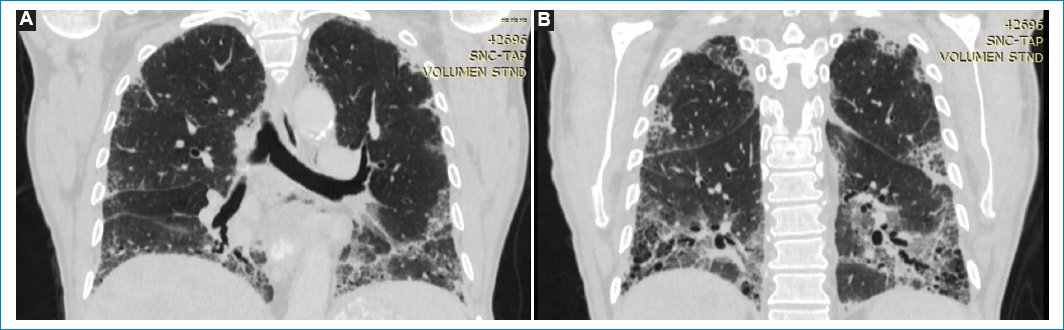

La TC de tórax actual demuestra infiltrados reticulares en ambos parénquimas pulmonares, acompañado de múltiples pequeñas imágenes quísticas de disposición subpleural conformando “patrón en panal de abejas” con predominio de ambos lóbulos inferiores. Se acompaña de bronquiectasias cilíndricas en ambos parénquimas, así como también infiltrado intersticial en vidrio esmerilado, siendo más evidente en las bases. Estos hallazgos se interpretaron como neumonía intersticial usual, lo cual no se observaba en estudios previos (Figs. 2 y 3).

Figura 3. (A, B) TC corte coronal en ventana para evaluar parénquima pulmonar, “patrón en panal de abejas” en ambos lóbulos inferiores. Se acompaña de bronquiectasias cilíndricas en ambos parénquimas.